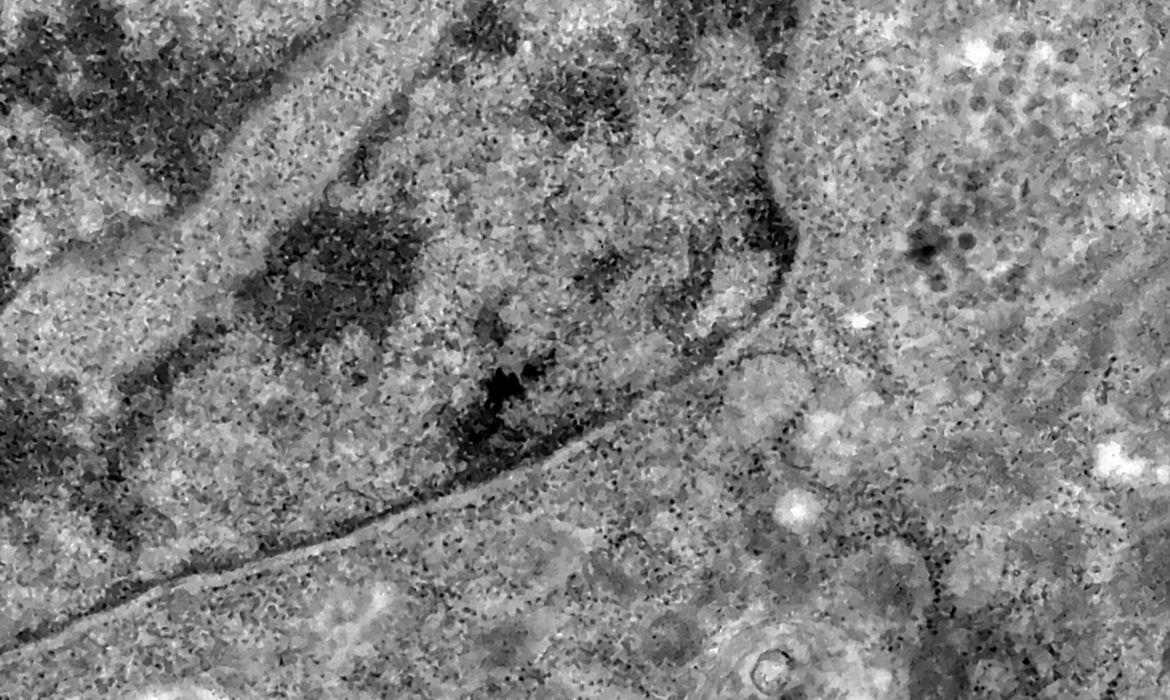

Legenda: Variante do coronavírus foi descoberta na África do Sul

Foto: Débora Barreto/Fiocruz